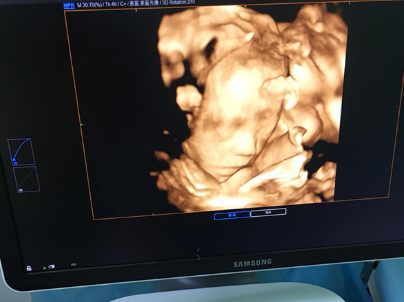

试管婴儿技术,也就会是试管受孕-胚胎移植(试管婴儿(IVF)-ET),是一种辅助生育技术。这个技术通过将精子和卵子在体外进行结合,造成胚胎,然后将胚胎移植回母体,以达成受孕的目的。跟着技术的继续前进,试管婴儿技术已然帮助很多家庭完成了生育愿望。